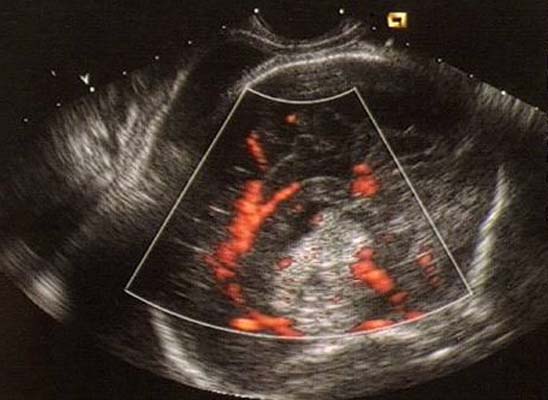

Crâniopharyngiome